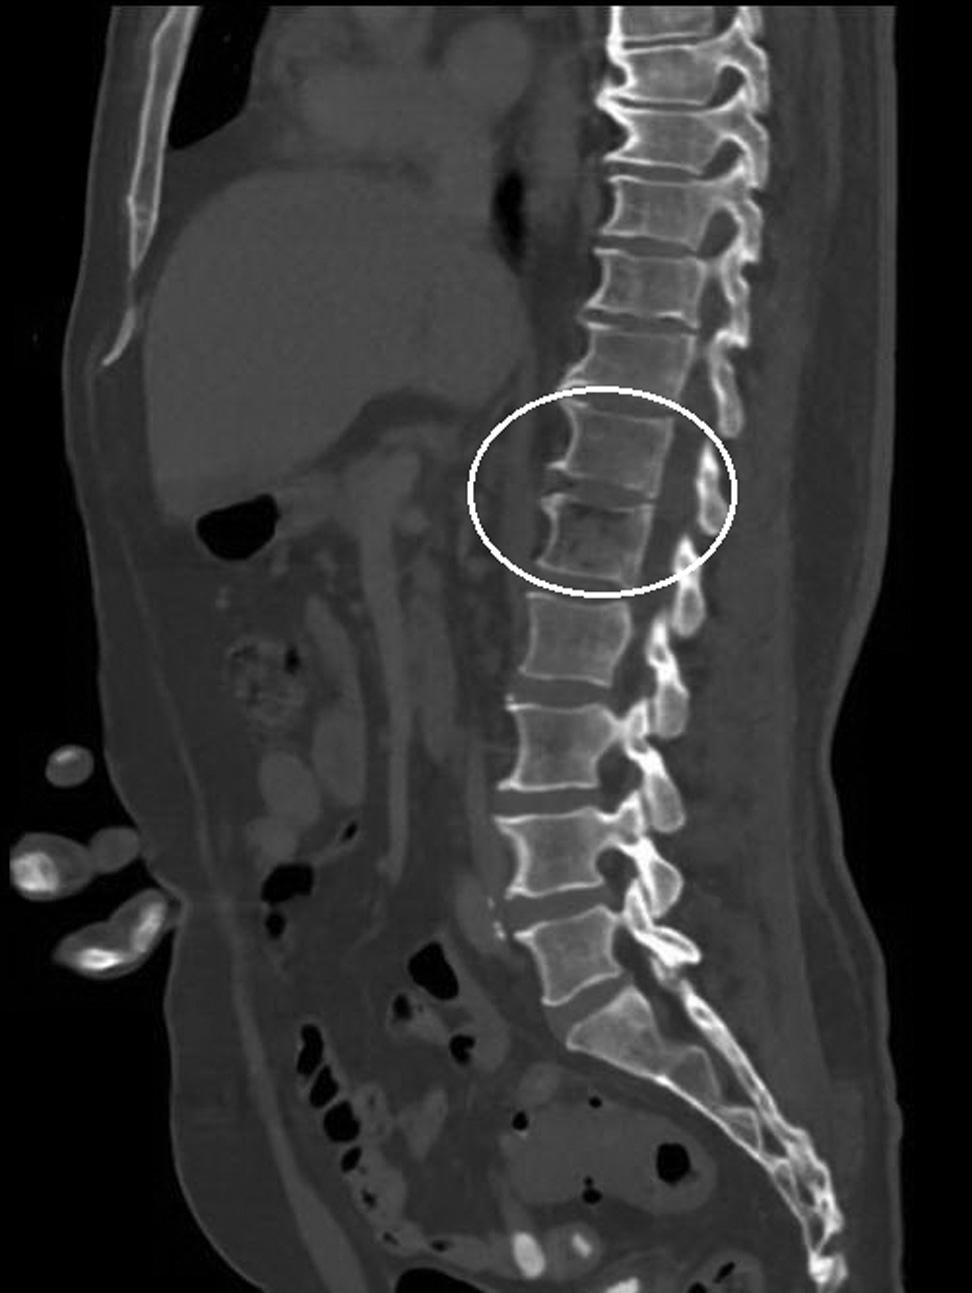

Emergentcomputedtomographyoftheabdomenand pelvisrevealedalargeleftretroperitonealandperitoneal hematomasecondarytoleftRAArupture,aswellasconcern fordevelopingsplenicinfarctsintheleftlowerrenalpole (Image).Thepatientwastakenemergentlytotheoperating room(OR)forexploratorylaparotomywithintwohoursof EDarrival.Sheunderwentsuprarenalcross-clampingwith repairoftheleftrenalarteryandligationofrenalvessels.She returnedtotheORtwodayslaterforleftnephrectomyand abdominalclosure.Shewasextubatedandtransferredtothe floor.Shewasdischargedhometwodayslaterin goodcondition.